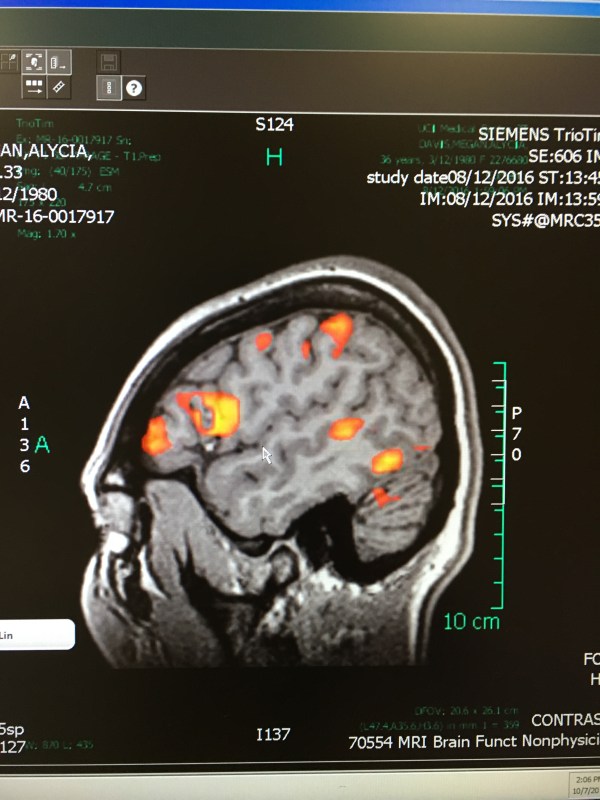

I have a malformation/lesion in my front, left temporal lobe. I might've had it since birth or acquired it through some sort of head trauma; the former is more likely than the latter. However, through MRIs over the years, it’s changed a bit and at some point there was a bleed off of the malformation...